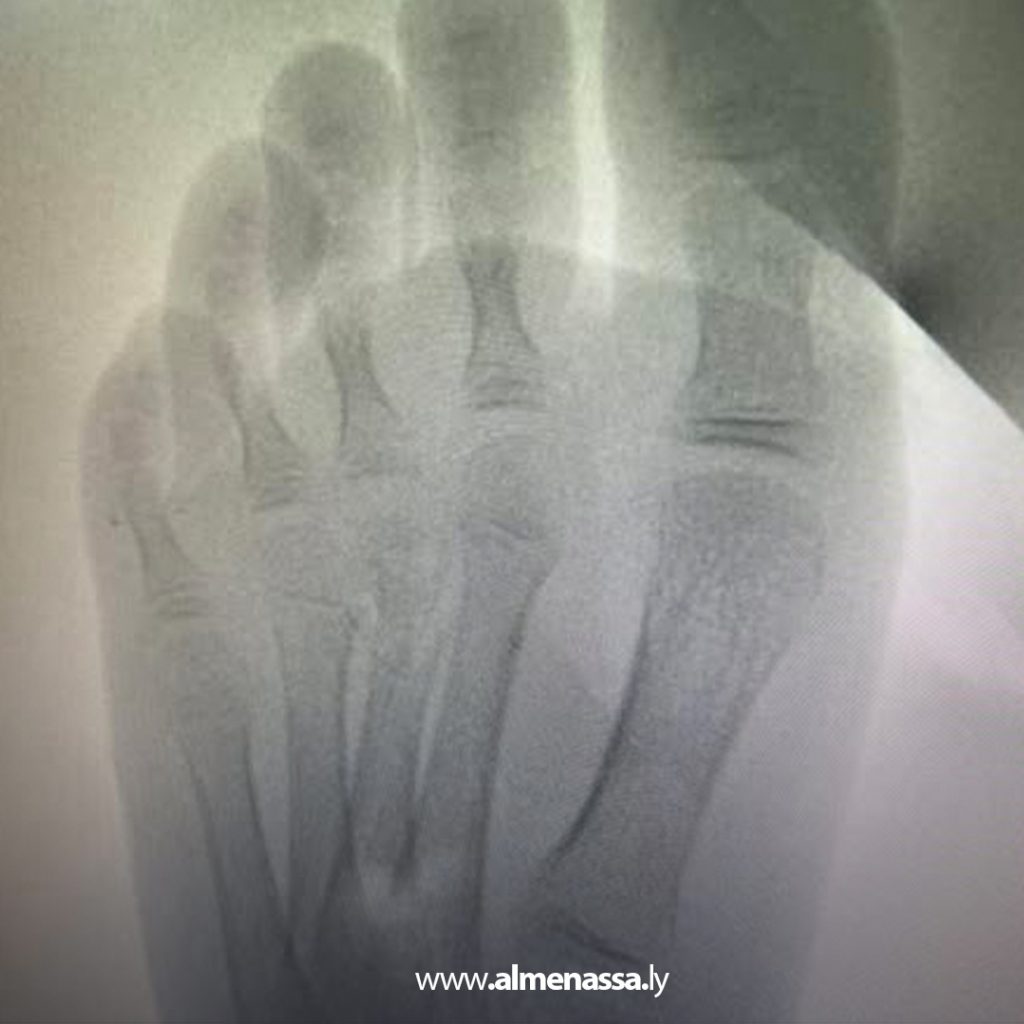

وتحدث استشاري جراحة العظام عن حالة تمكنت فيها الإبرة من ثقب العظم والدخول في العظم وبالتحديد داخل نخاع عظم مشط القدم مما يجعل هناك صعوبة كبيرة في استخراجها مبينا أنه كانت هناك محاولة لم يكتب لها النجاح لاستخراج هذه الابرة في المستشفى لصعوبة الوصول إليها.

ولفت لنقي إلى أن هذه العملية تتطلب فتح نافذة صغيرة داخل عظم المشط الثالث للقدم باستعمال صورة الأشعة السينية أثناء العملية لتحديد مكان الإبرة بشكل دقيق ومن ثم استخراج إبرة الخياطة المكسورة من داخل تجويف العظم لهذه المريضة ذات 5 سنوات.